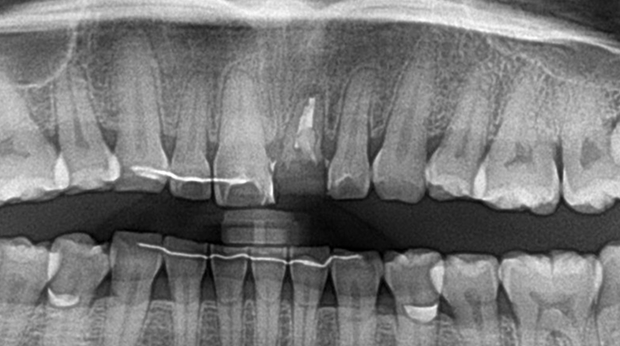

임플란트와 사랑니 발치는 외과적 시술로 잇몸을 절개하는 외과적 시술은

짧으면 짧을 수록 시술 후 붓기와 통증이 최소화됩니다.

치과의사 경력 14년차 구강외과 전문의가 빠르고 안전하게, 아프지 않게 수술해 드립니다.

치과경력 14년차 구강외과 전문의